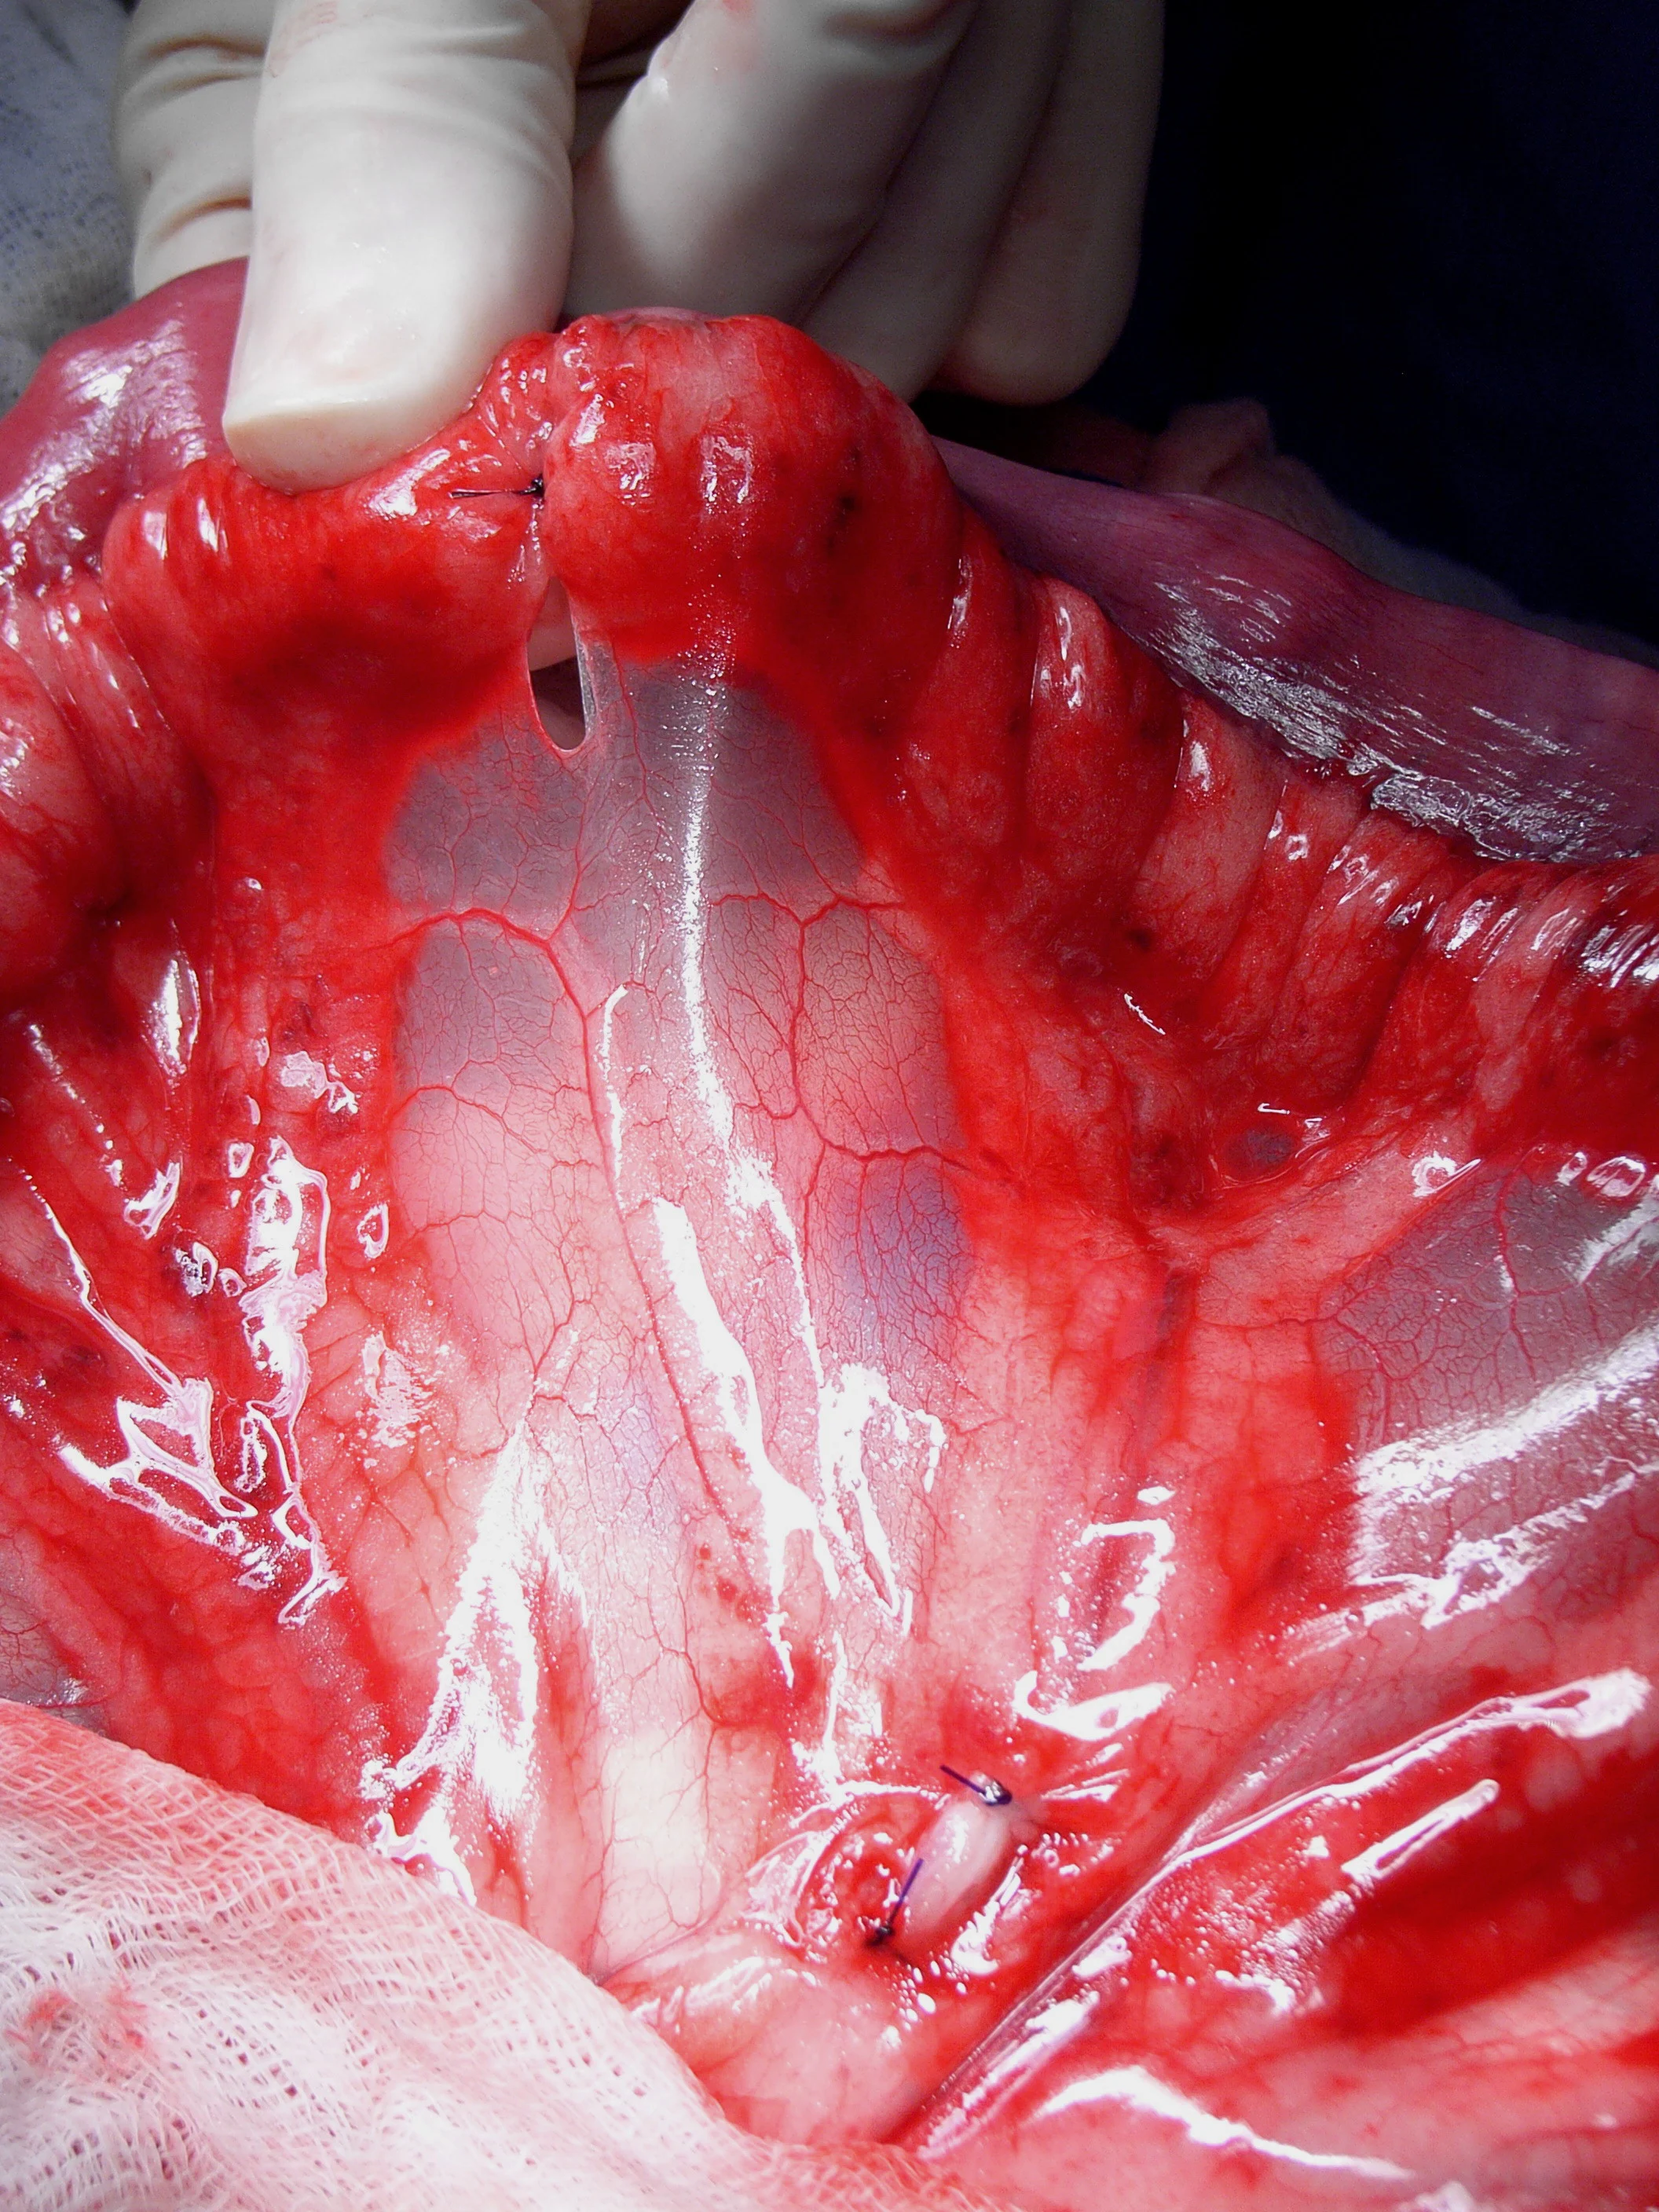

Manually milk the contents from the bowel segment and occlude the lumen orad and aborad with noncrushing Doyen tissue forceps (a) or assistant’s fingers. This is done to prevent leakage of intestinal contents into the surgical site. Avoid crushing the bowel wall or mesenteric vasculature with this procedure. Place crushing forceps (b) just adjacent and inside the proposed transection, leaving at least 2 cm of healthy tissue between the 2 clamps.

These crushing forceps are often placed at a 30-degree angle to the perpendicular, with the antimesenteric aspect away from the lesion. The angled transection ensures adequate perfusion of the antimesenteric border and obtains a larger luminal diameter for suturing (see Luminal Disparity).